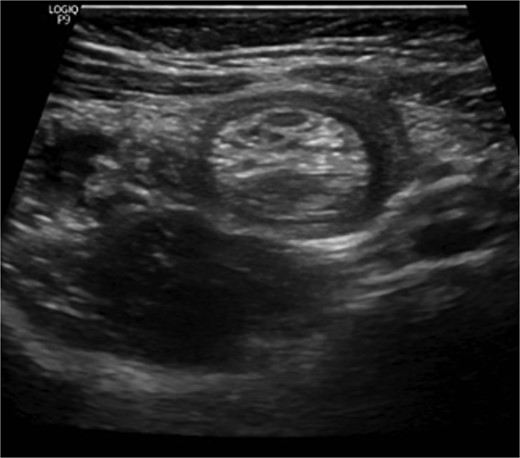

The blood tests showed raised inflammatory markers. An abdominal ultrasound confirmed the presence of intussusception (Fig. 2). A decision was made for a laparoscopic reduction of the intussusception and inspecting for a leading point. A MD was demonstrated and resected accordingly (Fig. 3). The location of intussusception was at the ileo-cecal area. The affected bowel was viable. The position of the MD was in the terminal ileum and it was the lead point for the intussusception. No lymph node involvement. Also, a tumor located at the base of the MD ~4 mm from the resection margin, was found and resected.

Ultrasound of the abdomen showed a target sign of intussusception (5th attack).